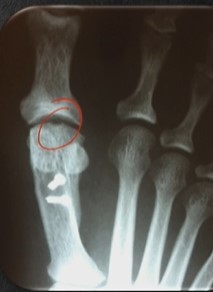

Achados de imagem?

A

RX:

- Artrose

- Osteófito dorsal (clássico)

- Depressão no domo da cabeça (1º sinal - anexo)

RM: dúvida se origem traumática

- Lesão condral